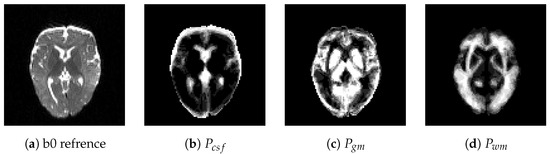

2.4.1. The NMF-Based Visual Appearance Model

Segmentation Results